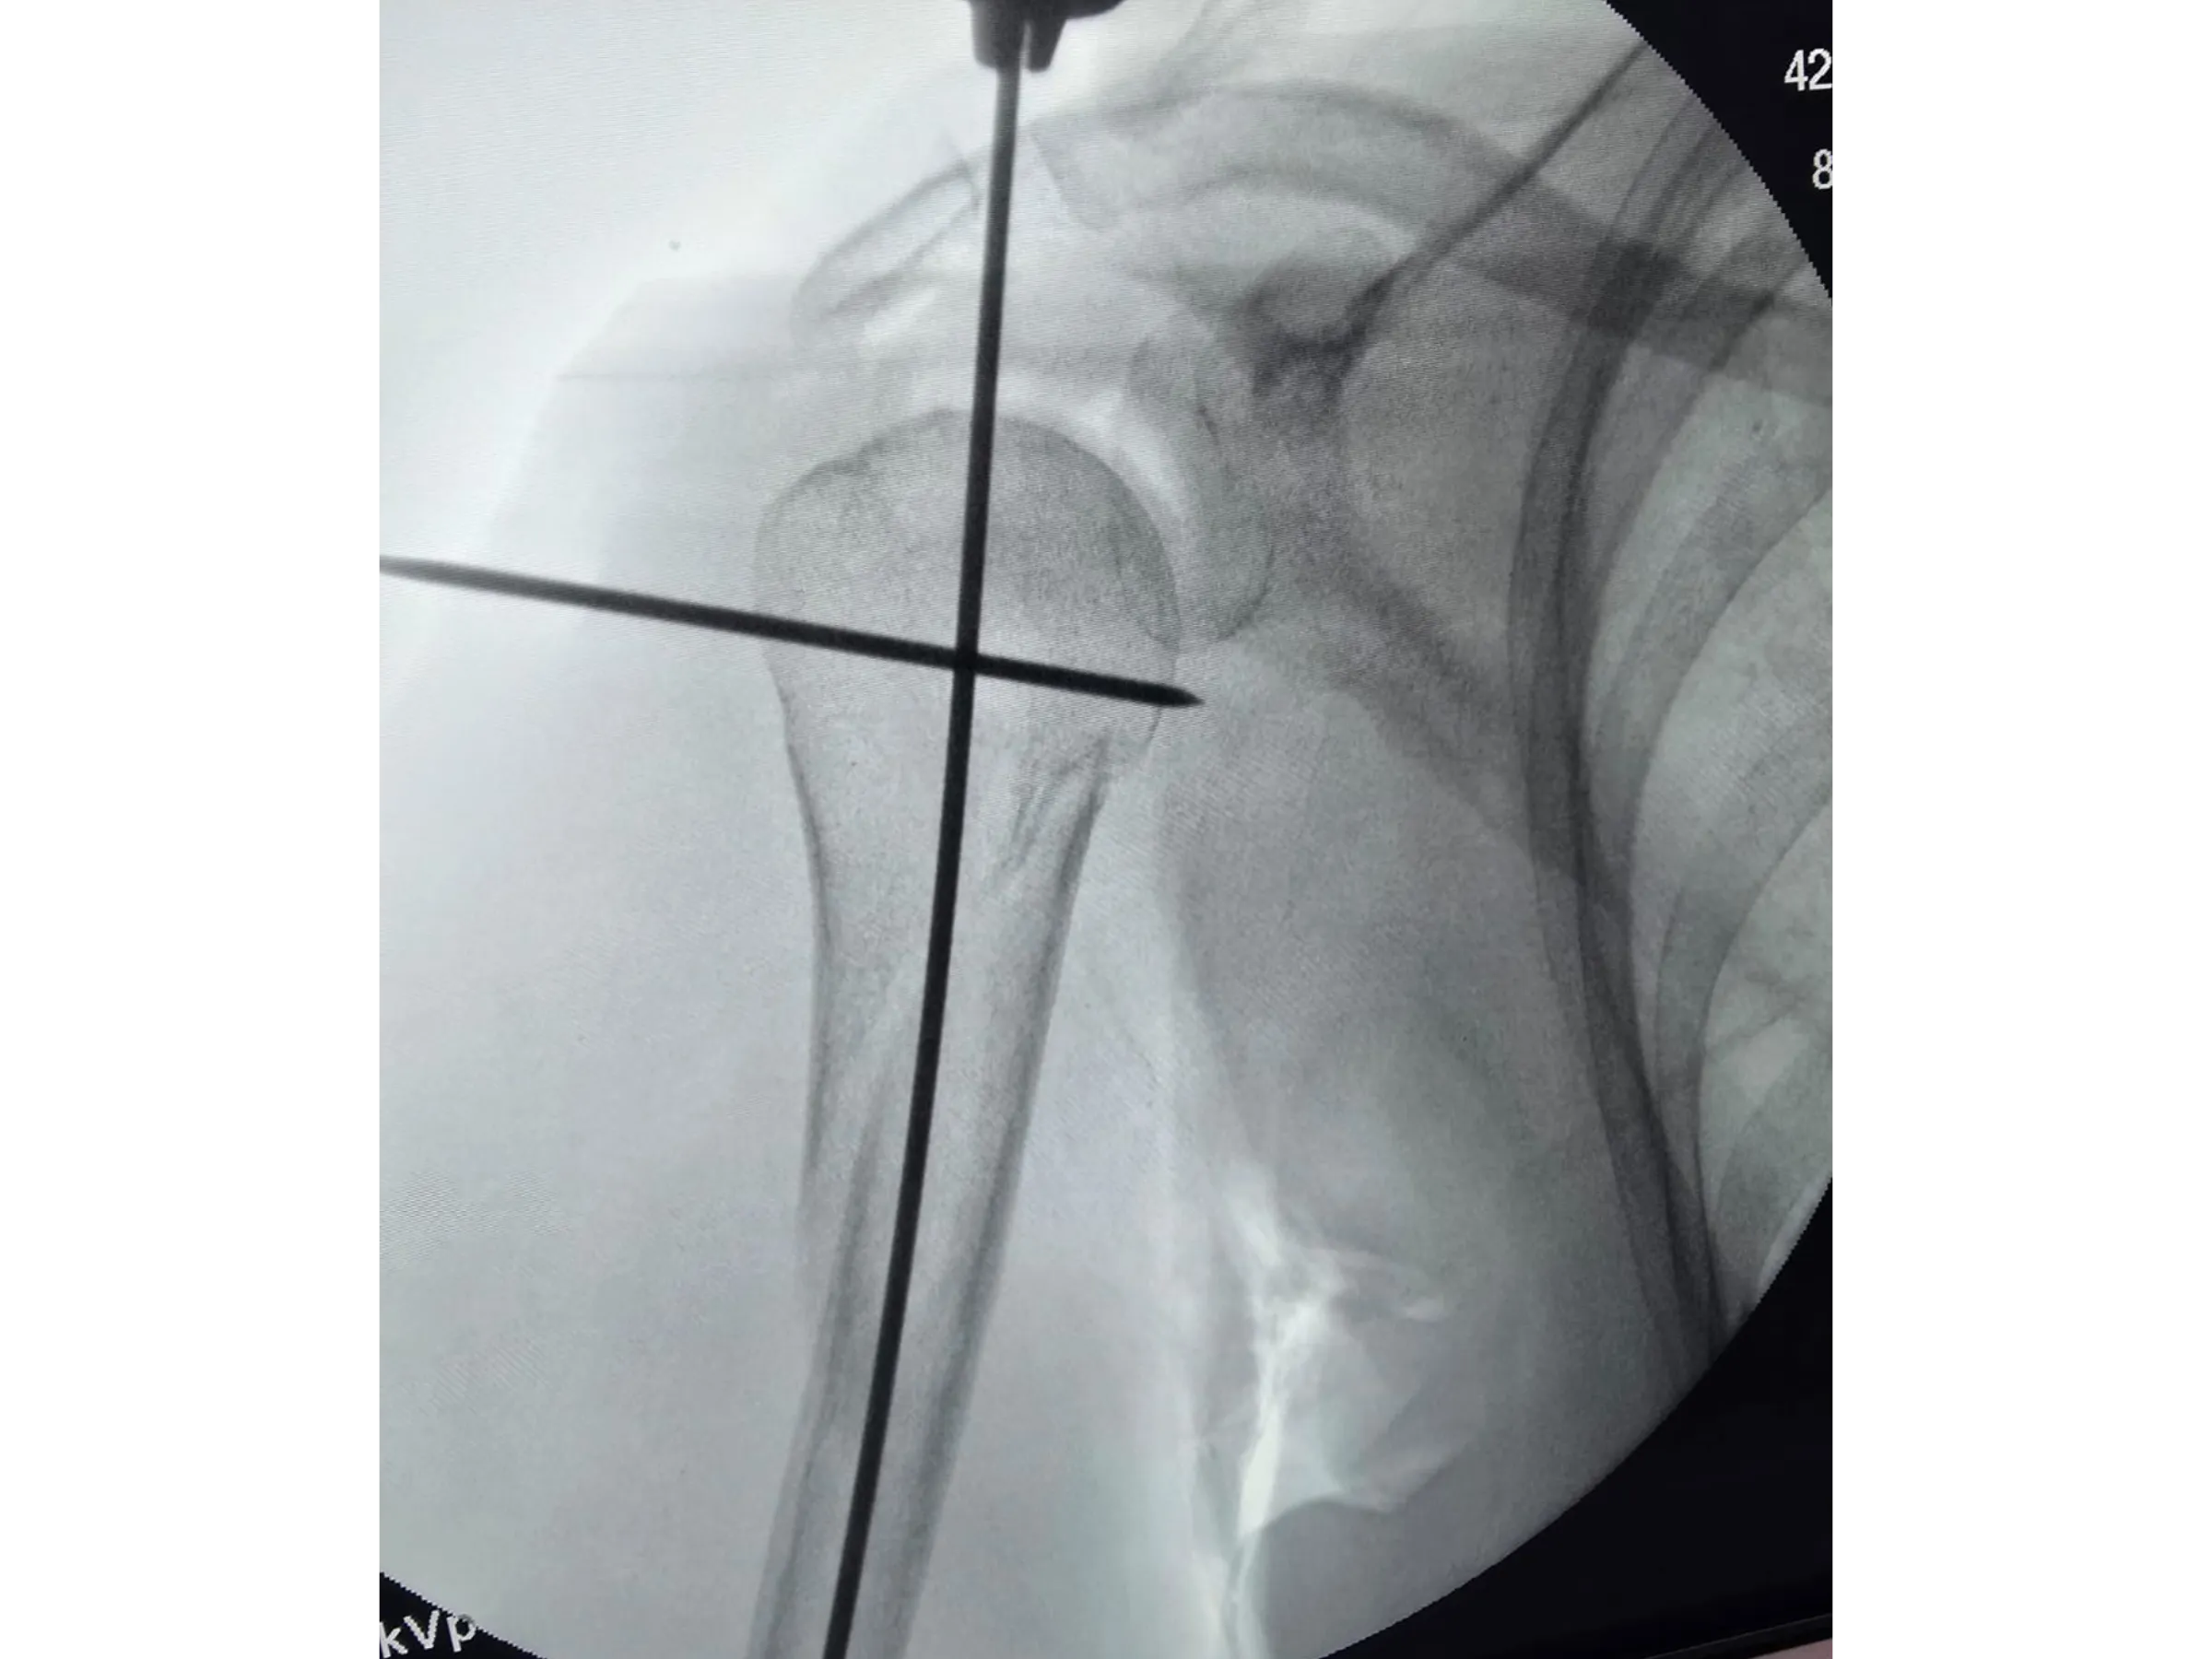

- Anatomical marking and guide wire insertion with radiographic control.

- Precise Radiographic Marking: Use of Kirschner wires and dermography for sagittal alignment.

- Joystick for Humeral Head Alignment: Safe manipulation for correcting the angle and centering of the entry point.